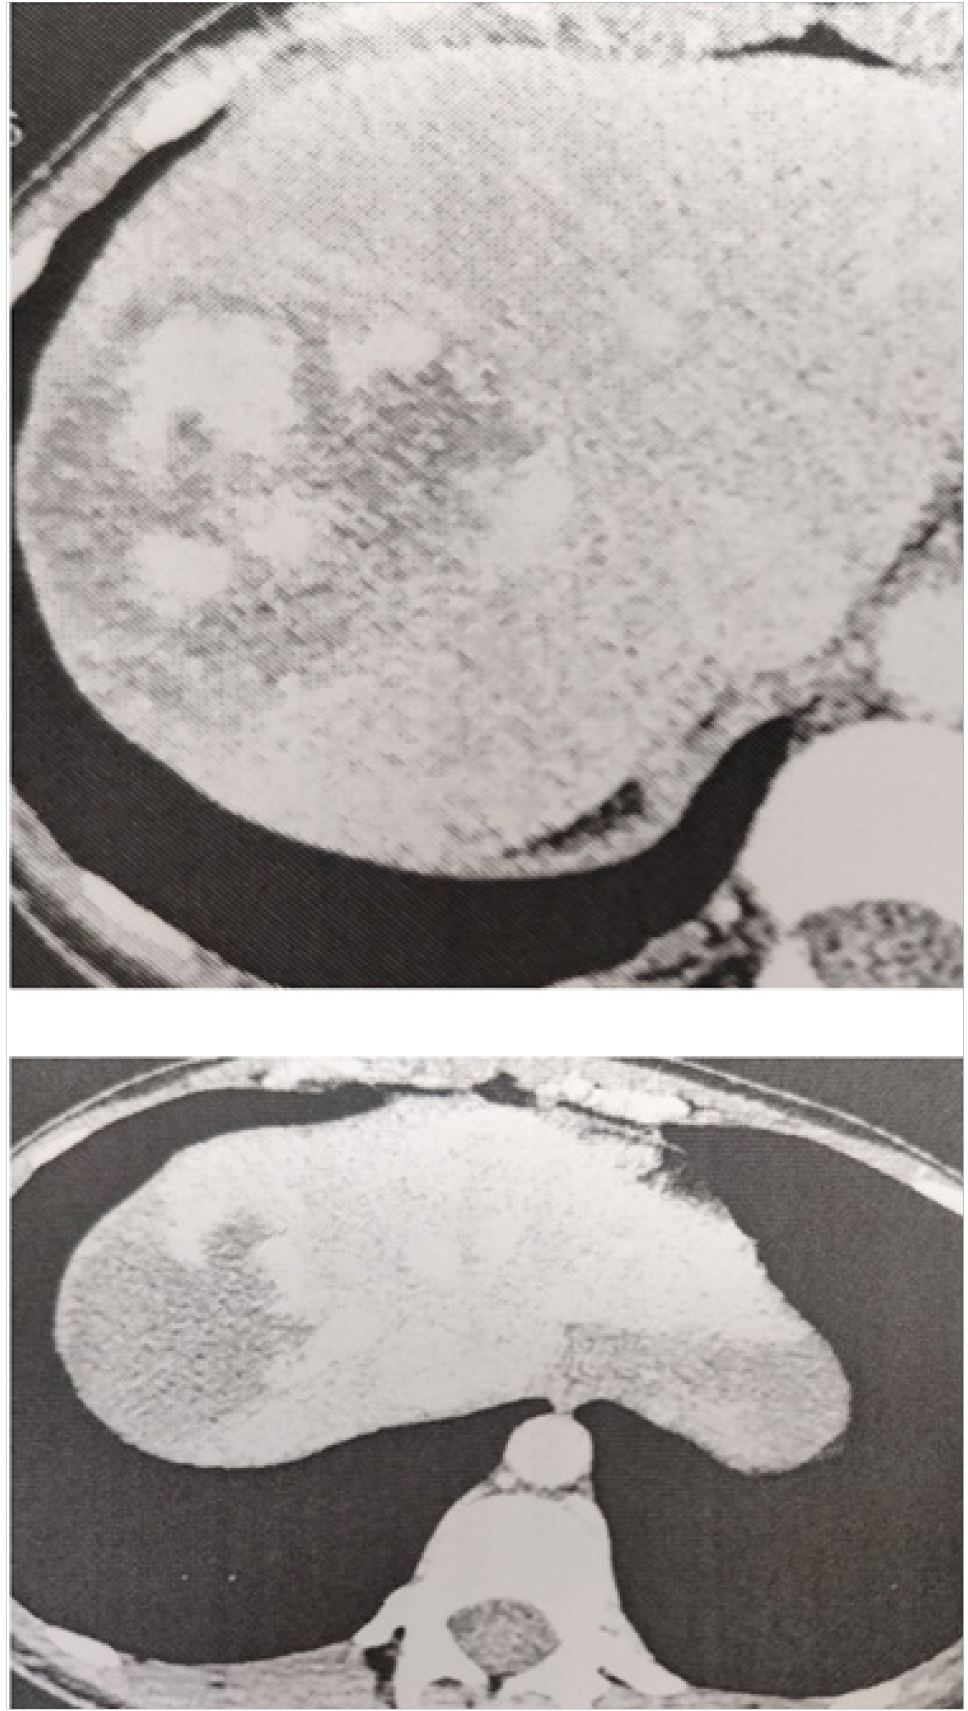

МЕТОДИКА ИССЛЕДОВАНИЯ

Представляем клинический случай лечения пациентки 1985 года рождения, которая обратилась в консультативную поликлинику ККБСМП имени М.А. Под- горбунского в июне 2019 г. При осмотре пациентка предъявляла жалобы на постоянный дискомфорт в эпигастрии, правом подреберье, тошноту, одышку. Больная амбулаторно наблюдается по поводу гемангиом печени, периодически выполняет УЗИ органов брюшной полости в динамике, тогда максимальный размер их достигал 2,5–3 см. При объективном осмотре состояние пациентки легкой степени тяжести. Кожные покровы телесного цвета. Дыхание везикулярное, хрипов нет, ЧДД 18 в минуту. Гемодинамика стабильная. Живот симметричный, участвует в акте дыхания, не вздут, при пальпации безболезненный во всех отделах, объемных образований, инфильтратов не пальпируются. Перитонеальные симптомы отрицательные. Стул ежедневный, диурез не нарушен. По данным последнего ультразвукового исследования в проекции в проекции 6–7 сегментов печени имеется гемангиома 8 см в максимальном диаметре, в проекции 8 сегмента печени гемангиома 2 см в максимальном диаметре измерения. Больная была госпитализирована в отделение. При обследовании результаты общего анализа крови, общего анализа мочи, биохимического анализа крови, коагулограммы крови в норме. Фиброгастродуоденоскопия, фиброколоноскопия без органической патологии. Выполнено ультразвуковое исследование и компьютерная томография с болюсным контрастированием органов брюшной полости, по результатам которых печень расположена обычно, краниокаудальный размер печени 157 мм, контуры четкие, ровные, портальной и билиарной гипертензии нет, в проекции 7-го сегмента печени имеется объемное образование до 8 см в размерах, тесно прилегает к правой печеночной вене, рядом расположены еще 2 образования до 2,5 см, также имеется образование до 2 см в проекции S4 и до 4 см в S3 печени, тип контрастирования образований характерен для гемангиом (рис. 1). Выполнена КТ-волюмометрия паренхимы печени, объем которой составляет 1500 см³, объем гемангиом 190 см³, объем интактной паренхимы печени (1, 2, 3, 4-й сегменты печени) 250 см³.

Через 20 дней пациентка госпитализирована в отделение для обследования решения вопроса о проведении второго этапа хирургического лечения. Клинически и по результатам обследования состояние пациентки было удовлетворительное. По данным КТ волюмометрии печени, объем 1, 2, 3, 4-го сегментов печени составлял 450 см³, объем сочтен допустимым, для выполнения правосторонней гемигепатэктомии. Пациентке была выполнена правосторонняя гемигепатэктомия с атипичной резекцией 3-го сегмента печени.

Протокол операции. Под эндотрахеальным наркозом лапаротомия по Кальне. При ревизии левая доля с признаками гипертрофии, достаточных размеров, расценена как достаточная для обеспечения функции после резекции правой доли печени (рис. 3).